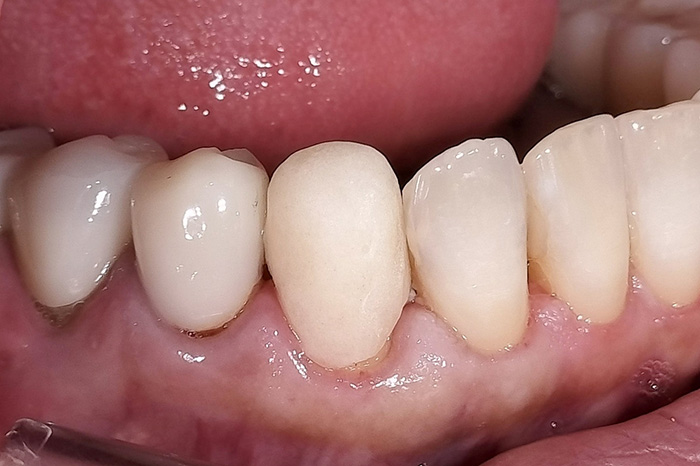

Before

After

【矯正治療】マウスピース型矯正装置(インビザライン)による全顎矯正

【補綴治療】詳細は表内の費用欄に掲載

【矯正治療】10か月

【補綴治療】約5か月

【矯正治療】12回

【補綴治療】14回

【矯正治療】¥957,000(税込)

【補綴治療】